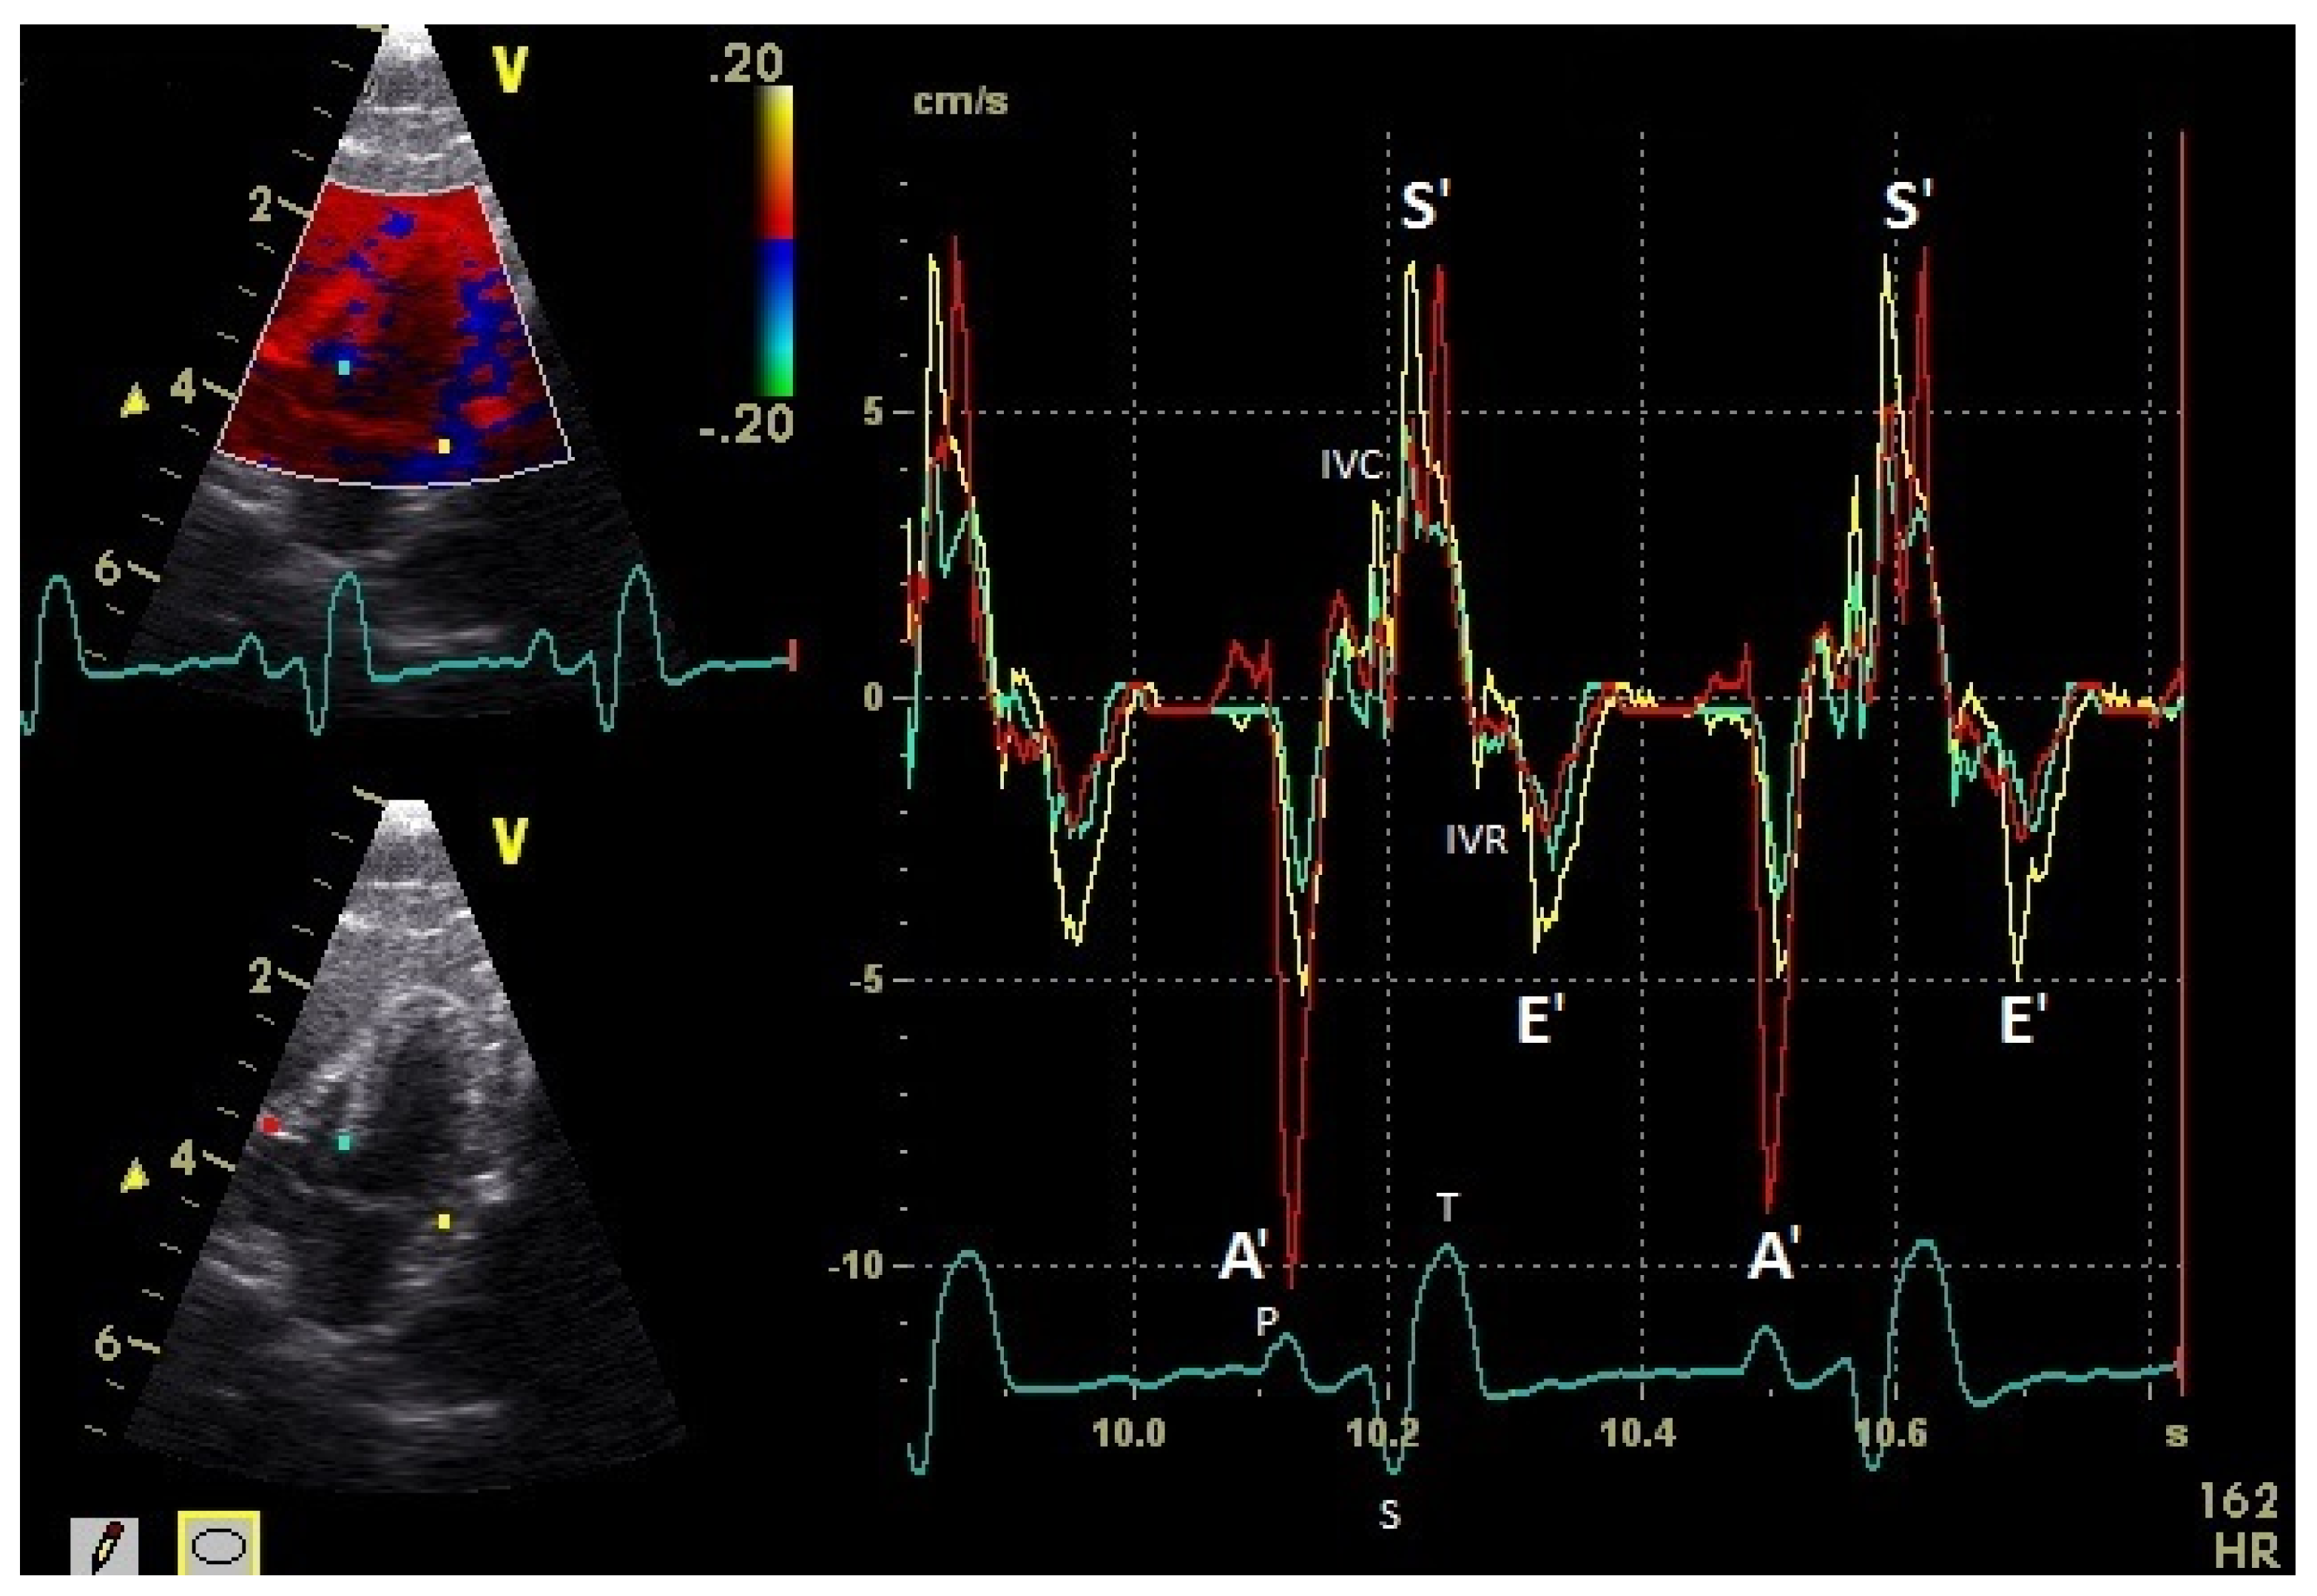

The positive S’ wave of the TDI curve (Figure 3 and Figure 4; ascending part of the S wave to the descending part of the T wave of the ECG) describes the systolic movement of the heart base toward the heart apex and represents the expulsion phase of the heart. In the middle of the S’ wave of the TDI, there is little movement of the heart apex toward the heart base and the myocardial velocities are negative (Figure 2). This movement in the middle part of the systole led to an irregular shape of the S’ wave in the TDI curve (Figure 3). The negative E’ wave (Figure 3 and Figure 4; after the T wave of the ECG) in the TDI curve describes the movement of the myocardium during the passive ventricular filling and the second negative A’ wave of the TDI curve (Figure 3 and Figure 4; P wave of the ECG) describes the movement of the myocardium in the active filling phases of the heart during the diastole away from the heart apex. Before and after the S’ wave, the TDI curve showed undirected deflections as a sign of isovolumetric contraction (IVC) and relaxation (IVR; Figure 3 and Figure 4). However, the transition between the A’ and S’ waves (IVC) and the S’ and E’ waves (IVR) could be flowing and sometimes difficult to see.

Figure 3.

Basal myocardial velocities in the four-chamber view measured by TDI: sample areas (Ø 2 mm): red: right ventricular free wall; yellow: left ventricular free wall; green: septum; early diastolic: E’ wave; late diastolic: A’ wave; systolic tissue velocities: S’ wave. Isovolumetric contraction: IVC; isovolumetric relaxation: IVR; HR: heart rate. Electrocardiogram: P: P wave; S: S wave; T: T wave.

The systolic and diastolic peak tissue velocities depending on the myocardial segment are shown in Table 1. In general, the highest myocardial velocities are visible at the atrioventricular valvular annulus in the basal segments. The velocities decrease significantly and continuously to the apex of the heart for the S’, E’, and A’ waves (p ≤ 0.001). Significant differences in the myocardial velocities could also be detected between the heart septum and the left and right free wall (Table 1).

In the examined pigeons, the systolic velocities (S’ wave) of the left and right free wall were significantly higher (p ≤ 0.001; Table 1) than the S’ wave velocities of the heart septum. The S’ wave velocities of the right free wall were not significantly different to the velocities of the left free wall.

The diastolic E’ wave velocities (passive diastolic filling) of the left and right free wall were significantly higher than in the septum (p ≤ 0.001). There were no significant differences between the E’ wave velocities of the left and right free wall. The A’ wave velocities in all heart segments were higher than the E’ wave velocities (p ≤ 0.001). The peak A’ wave velocities of the right free wall were significantly higher than the velocities of the left free wall (p ≤ 0.02). The left and right free wall velocities were significantly higher than the velocities of the heart septum (p ≤ 0.001).